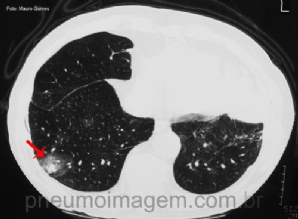

CASO CLÍNICO #43

Esse sinal tomográfico está associado a uma grave complicação em imunocomprometidos. Qual o nome do sinal e a qual doença ele se relaciona? Deixe os seus comentários abaixo! ***** This tomographic signal is associated with a serious complication in immunocom...